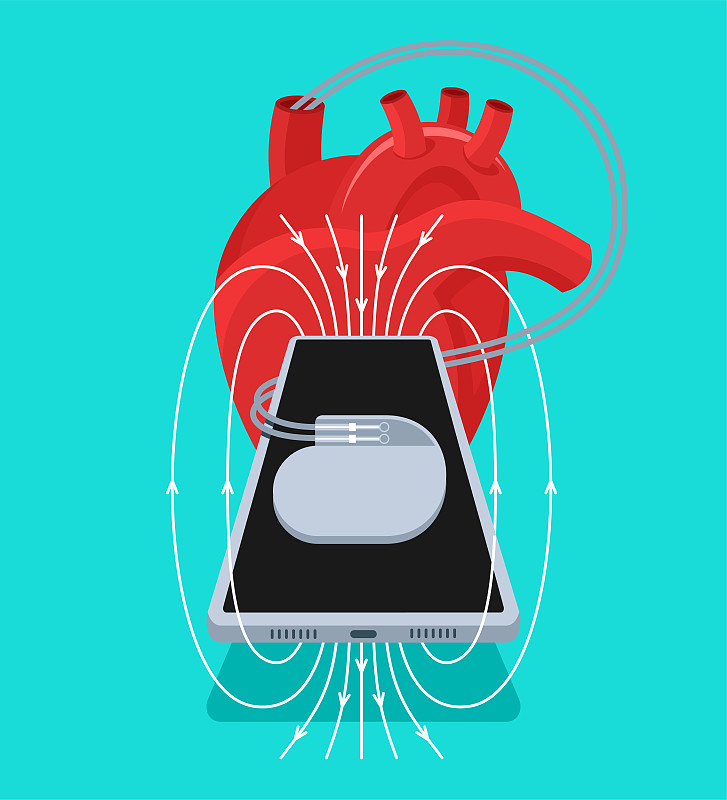

心脏起搏器详情

JPG

Pacemaker详情

SVG

带有电引线的起搏器详情

JPG

起搏器详情

JPG